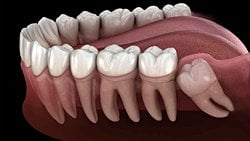

Yirmi yaş dişlerinin sıklıkla gömülü kalırlar, çıktıkları zaman doğru şekilde çıkmazlar ve diğer dişlere sürtünerek onların yapısını bozabilirler. Bu nedenle de ağrı ve enfeksiyona neden oldukları bilinmektedir. Bunun haricinde ise hiçbir işlevleri bulunmamaktadır. Dolayısıyla ağrıya neden oldukları zaman, diş hekimleri tarafından çekilerek hasta rahatlatılabilmektedir. 20 yaş dişleri çekilen kişilerin ağız fonksiyonlarında hiçbir azalma olmamaktadır. Aşağıda bu dişleri görmektesiniz: